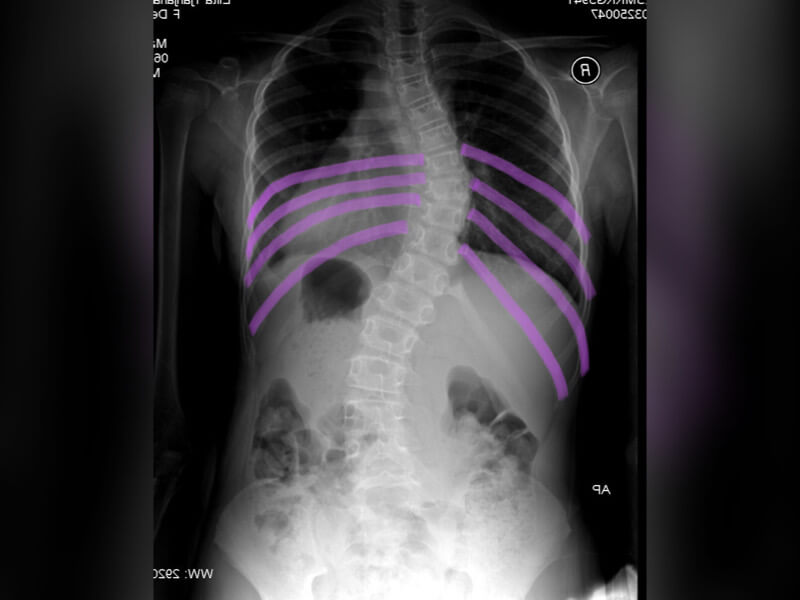

我們再來看一個X光片,現在我們可以知道,心臟的位置在這裡的情況下,這是一張背面的X光影像,所以是一個胸右彎的案例,可以看到左右各畫了四條線,左側肋骨的上下距離會比較緊密,但是右側肋骨的上下距離就會變得比較寬。

胸椎側彎對於肋骨的影響,大家會覺得胸椎側彎跟肋骨到底有甚麼關係呢?先了解,沒有脊椎側彎的人會是呈現對稱的肋骨,有肋骨的地方就是胸椎的區域,一個胸椎脊椎我們比喻像是一個樂高積木好了,它兩邊都會有一對翅膀,所以胸椎它有12節脊椎,那它就會有12對肋骨,這是正常的脊椎,它的左右兩邊的距離的寬度,都會是比較對稱的,但是如果是脊椎側彎的患者呢?會像這張圖右側的上下肋骨的距離,它就會相對來講被撐開,但是左側上下肋骨的距離,就會慢慢的靠攏在一起,會比較緊密。

一個胸椎向右側彎的案例,他的右側的肋骨,會被撐開,往背後凸起來,所以在檢查的時候,就會常常看到:「ㄟ 他的右後背怎麼會這樣鼓鼓的、凸凸的,左邊的背摸起來有一點凹下去」 ,這就是胸椎側彎對於肋骨的影響,特別是在身體前彎的時候,他會有一個單側隆凸最明顯的地方,也是肋骨間相對距離比較寬的區域喔。